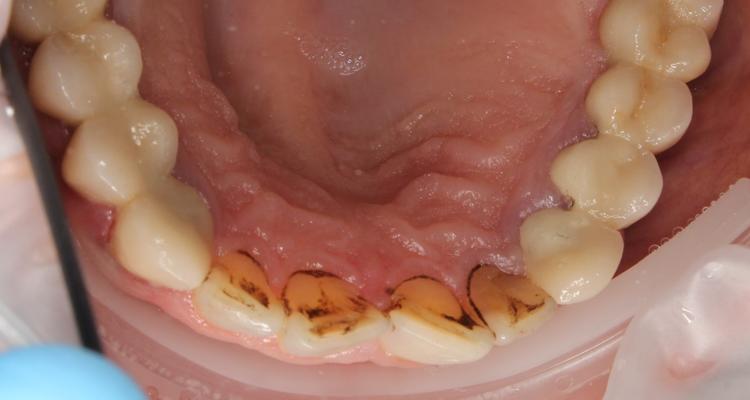

Профессиональная гигиена нижней фронтальной группы зубов фото доПрофессиональная гигиена нижней фронтальной группы зубов фото после

Посмотреть фото «до»

Профессиональная гигиена нижней фронтальной группы зубов

Во время процедуры был удален пигментированный зубной налет и камень, а также проведена полировка зубов.